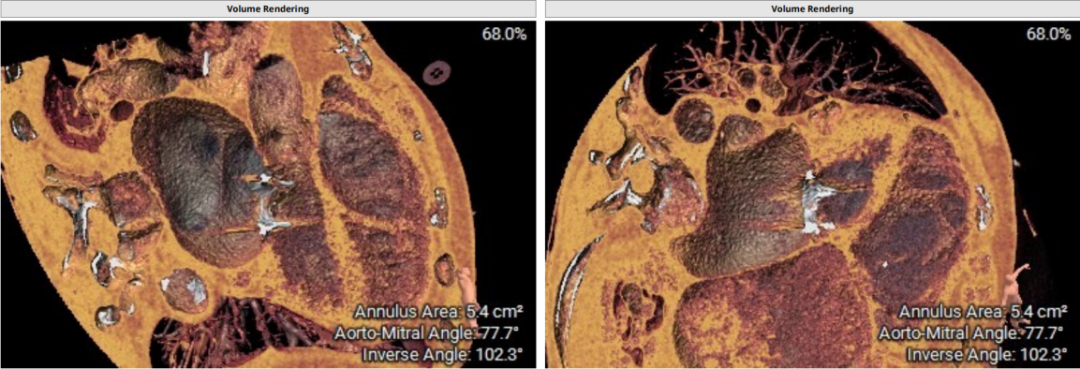

术前CT评估示:患者二尖瓣生物瓣置换术后,原生物瓣型号未知,生物瓣金属环平均内径25.9mm,外径31.5mm,瓣架高度15.9mm;

左心室和二尖瓣轴线角度:135°;

左室大小:95.3*36.5*34.2mm;

模拟27mm瓣膜植入情况:

主动脉-二尖瓣角度:102.3°;

术中建议造影角度:RAO 58°/CRA 44°;RAO 49°/CRA 62°。